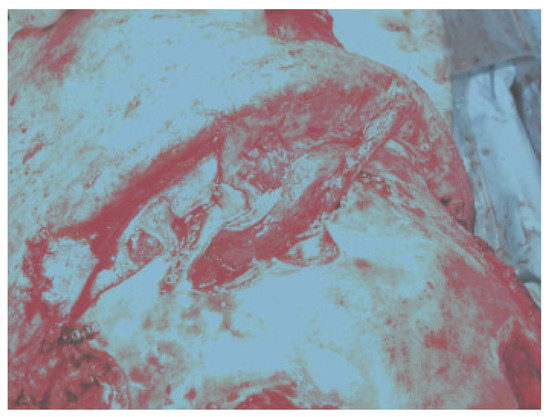

The most common skull-base complication encountered with frontal sinus fractures is mucocele (Figure 4). This is usually related to injury of the nasofrontal ostia (ducts) that is undiagnosed or poorly treated. The frontal sinus mucosa can be tenacious and if left behind after a frontal sinus fracture repair can manifest as a mucocele many years later (Figure 5) [18,19]. Mucopyocele is simply an infected mucocele and should be included in this category.

Figure 5.

The frontal sinus mucosa is tenacious. The mucosa looks black in this frontal sinus fracture with extension into the orbit. It is ciliated pseudostratified columnar epithelium with unidirectional sweeping motion toward the nasofrontal ostia. The mucosa is densely adherent to the diplopic veins via the foramina of Breschet.